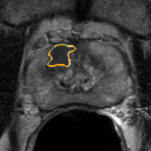

Radiomics uses quantitative medical imaging features to predict clinical outcomes. Currently, in a new clinical application, finding the optimal radiomics method out of the wide range of available options has to be done manually through a heuristic trial-and-error process. In this study we propose a framework for automatically optimizing the construction of radiomics workflows per application. To this end, we formulate radiomics as a modular workflow and include a large collection of common algorithms for each component. To optimize the workflow per application, we employ automated machine learning using a random search and ensembling. We evaluate our method in twelve different clinical applications, resulting in the following area under the curves: 1) liposarcoma (0.83); 2) desmoid-type fibromatosis (0.82); 3) primary liver tumors (0.80); 4) gastrointestinal stromal tumors (0.77); 5) colorectal liver metastases (0.61); 6) melanoma metastases (0.45); 7) hepatocellular carcinoma (0.75); 8) mesenteric fibrosis (0.80); 9) prostate cancer (0.72); 10) glioma (0.71); 11) Alzheimer's disease (0.87); and 12) head and neck cancer (0.84). We show that our framework has a competitive performance compared human experts, outperforms a radiomics baseline, and performs similar or superior to Bayesian optimization and more advanced ensemble approaches. Concluding, our method fully automatically optimizes the construction of radiomics workflows, thereby streamlining the search for radiomics biomarkers in new applications. To facilitate reproducibility and future research, we publicly release six datasets, the software implementation of our framework, and the code to reproduce this study.